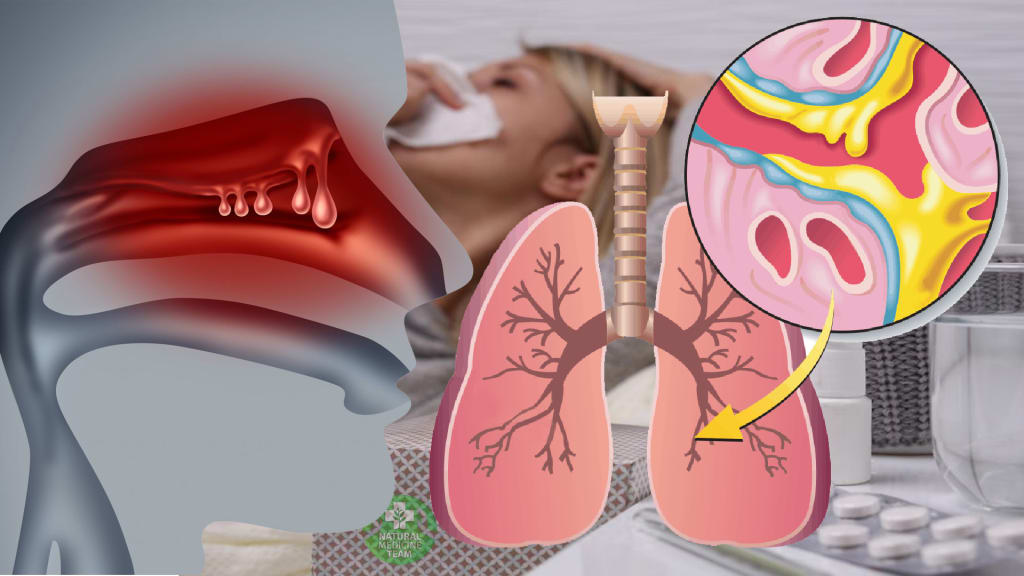

Mucus accumulations make you feel as if there’s something stuck in your throat. You sense an urge to clear your throat, and it’s really frustrating. This problem is usually created by infections in the upper respiratory tract, but mucus accumulations may be triggered by allergies, asthma, and heartburn.

Mucus prevents infections and keeps viruses and bacteria away from the body. In other words, having mucus in your throat is a normal thing. The real difficulty occurs when the mucus becomes thick and has an unusual color, such as dark yellow, green and brown.

The creation of mucus may be influenced by heartburn or acid reflux. Stomach acids go into the weak lower esophaegal sphincter, giving you a burning sensation. The throat becomes irritated, and you feel the “lump” in your throat.

This triggers the creation of mucus, giving you cold-like symptoms, such as cough, post-nasal drip, sinus issues, and sore throat. This issue goes undiagnosed often because it has the same symptoms as common colds and allergies.

The production of mucus may be extended by allergens. Pollen, dust, mites, animal dander and mold provoke your throat, and your body creates more mucus. Asthma is manifested through coughing and wheezing, but sufferers may also deal with the excessive creation of mucus.

In cases of bacterial and viral infections, the body creates excess mucus in order to trap the microorganisms. Sinusitis is a disease in which sinuses become inflamed and swollen. This infection also creates a post-nasal drip and thick, dark mucus.